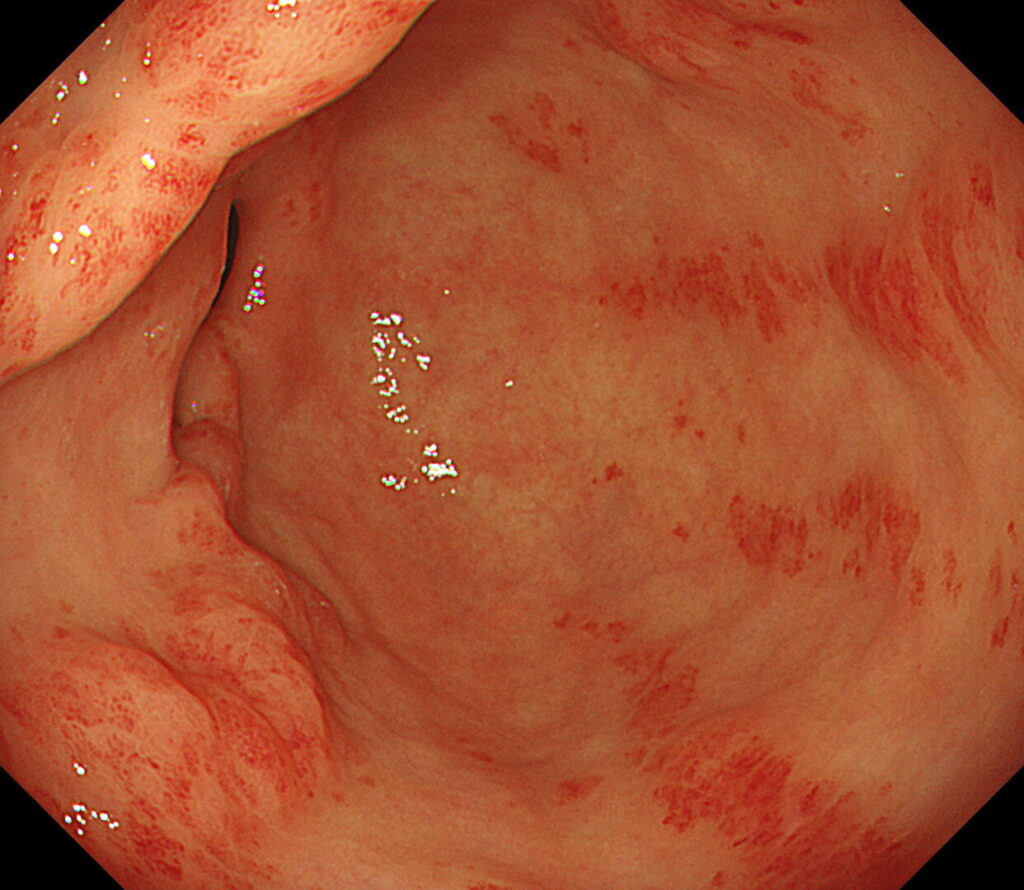

육안 소견만으로는 정상 점막과 거의 구별이 안 되는 경우가 많아,

- 색조의 미세한 차이

- 얕은 함몰

- 표면 패턴 변화

등을 근거로 조직검사를 시행합니다. 이 단계에서의 조직검사는 생명 예후와 직결되는 진단 과정입니다.